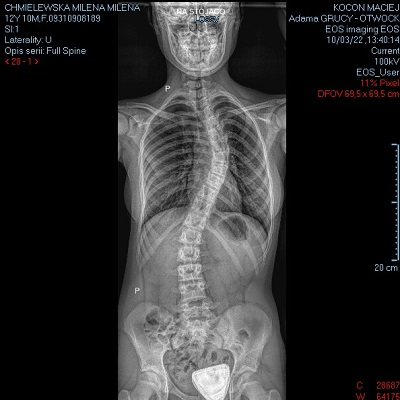

Nazywam się Milena, mam 13 lat. W lipcu zeszłego roku zdiagnozowano u mnie skoliozę idiopatyczną młodzieńczą, czyli o nieustalonej przyczynie. Choroba postępuje bardzo szybko

i obecnie skrzywienie się pogłębiło. Jest to skrzywienie kręgosłupa, które nie tylko powoduje defekt estetyczny, ale może przyczyniać się do przemieszczenia narządów wewnętrznych oraz silnych bólów. Leczenie możliwe wyłącznie operacyjnie. Operację mam zaplanowaną we Wrocławiu na 16 grudnia br.